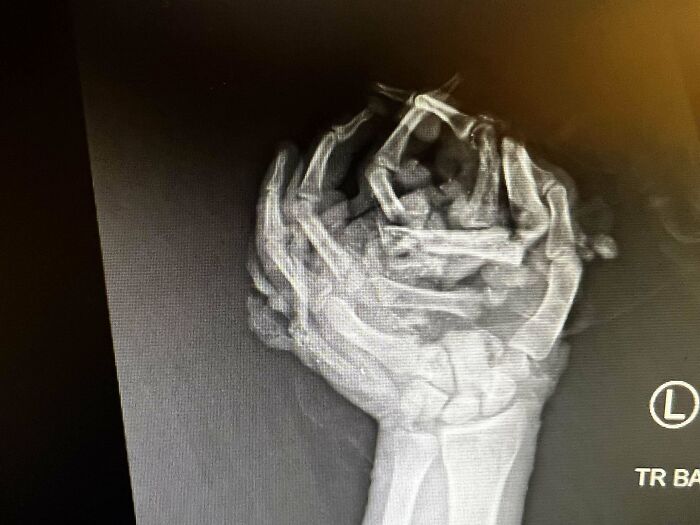

#18 My Left Hand Crushed From The Roof Of My Car After Flipping. X-Ray From The Night It Happened

Image credits: yeawrongperson